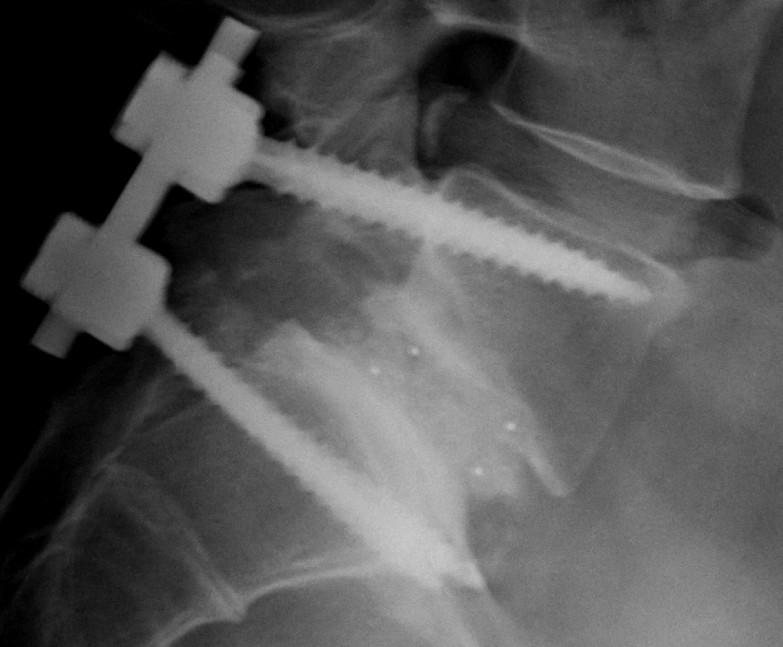

Диски с цефтазидимом и авибактамом, 10/4 Цефтазидим/авибактам 10/4 мкг . Реагенты in vitro на дисках для определения чувствительности микроорганизмов к антибиотикам . (5 картриджей по 50 дисков), CZA-14 Подробнее Заказать Заказать Свяжитесь с нами для составления индивидуального коммерческого предложения Описание

Диски для определения свойств микроорганизмов для in vitro диагностики: цефтазидим/ авибактам 10/4 мкг 1200807 Диски цефтазидим/ авибактам 10/4 кг BIO-RAD: УПАК: 1 200 .00: 2 .00: 2 400 .00